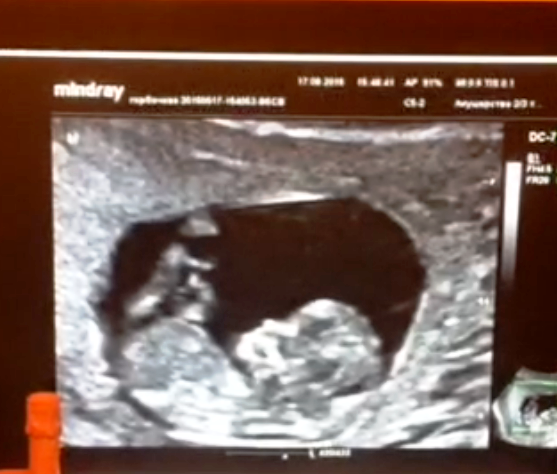

Вот и мы (правда 4 недели назад - 12 недель) лежим, балдеем у мамули в пузике и ножки задираем